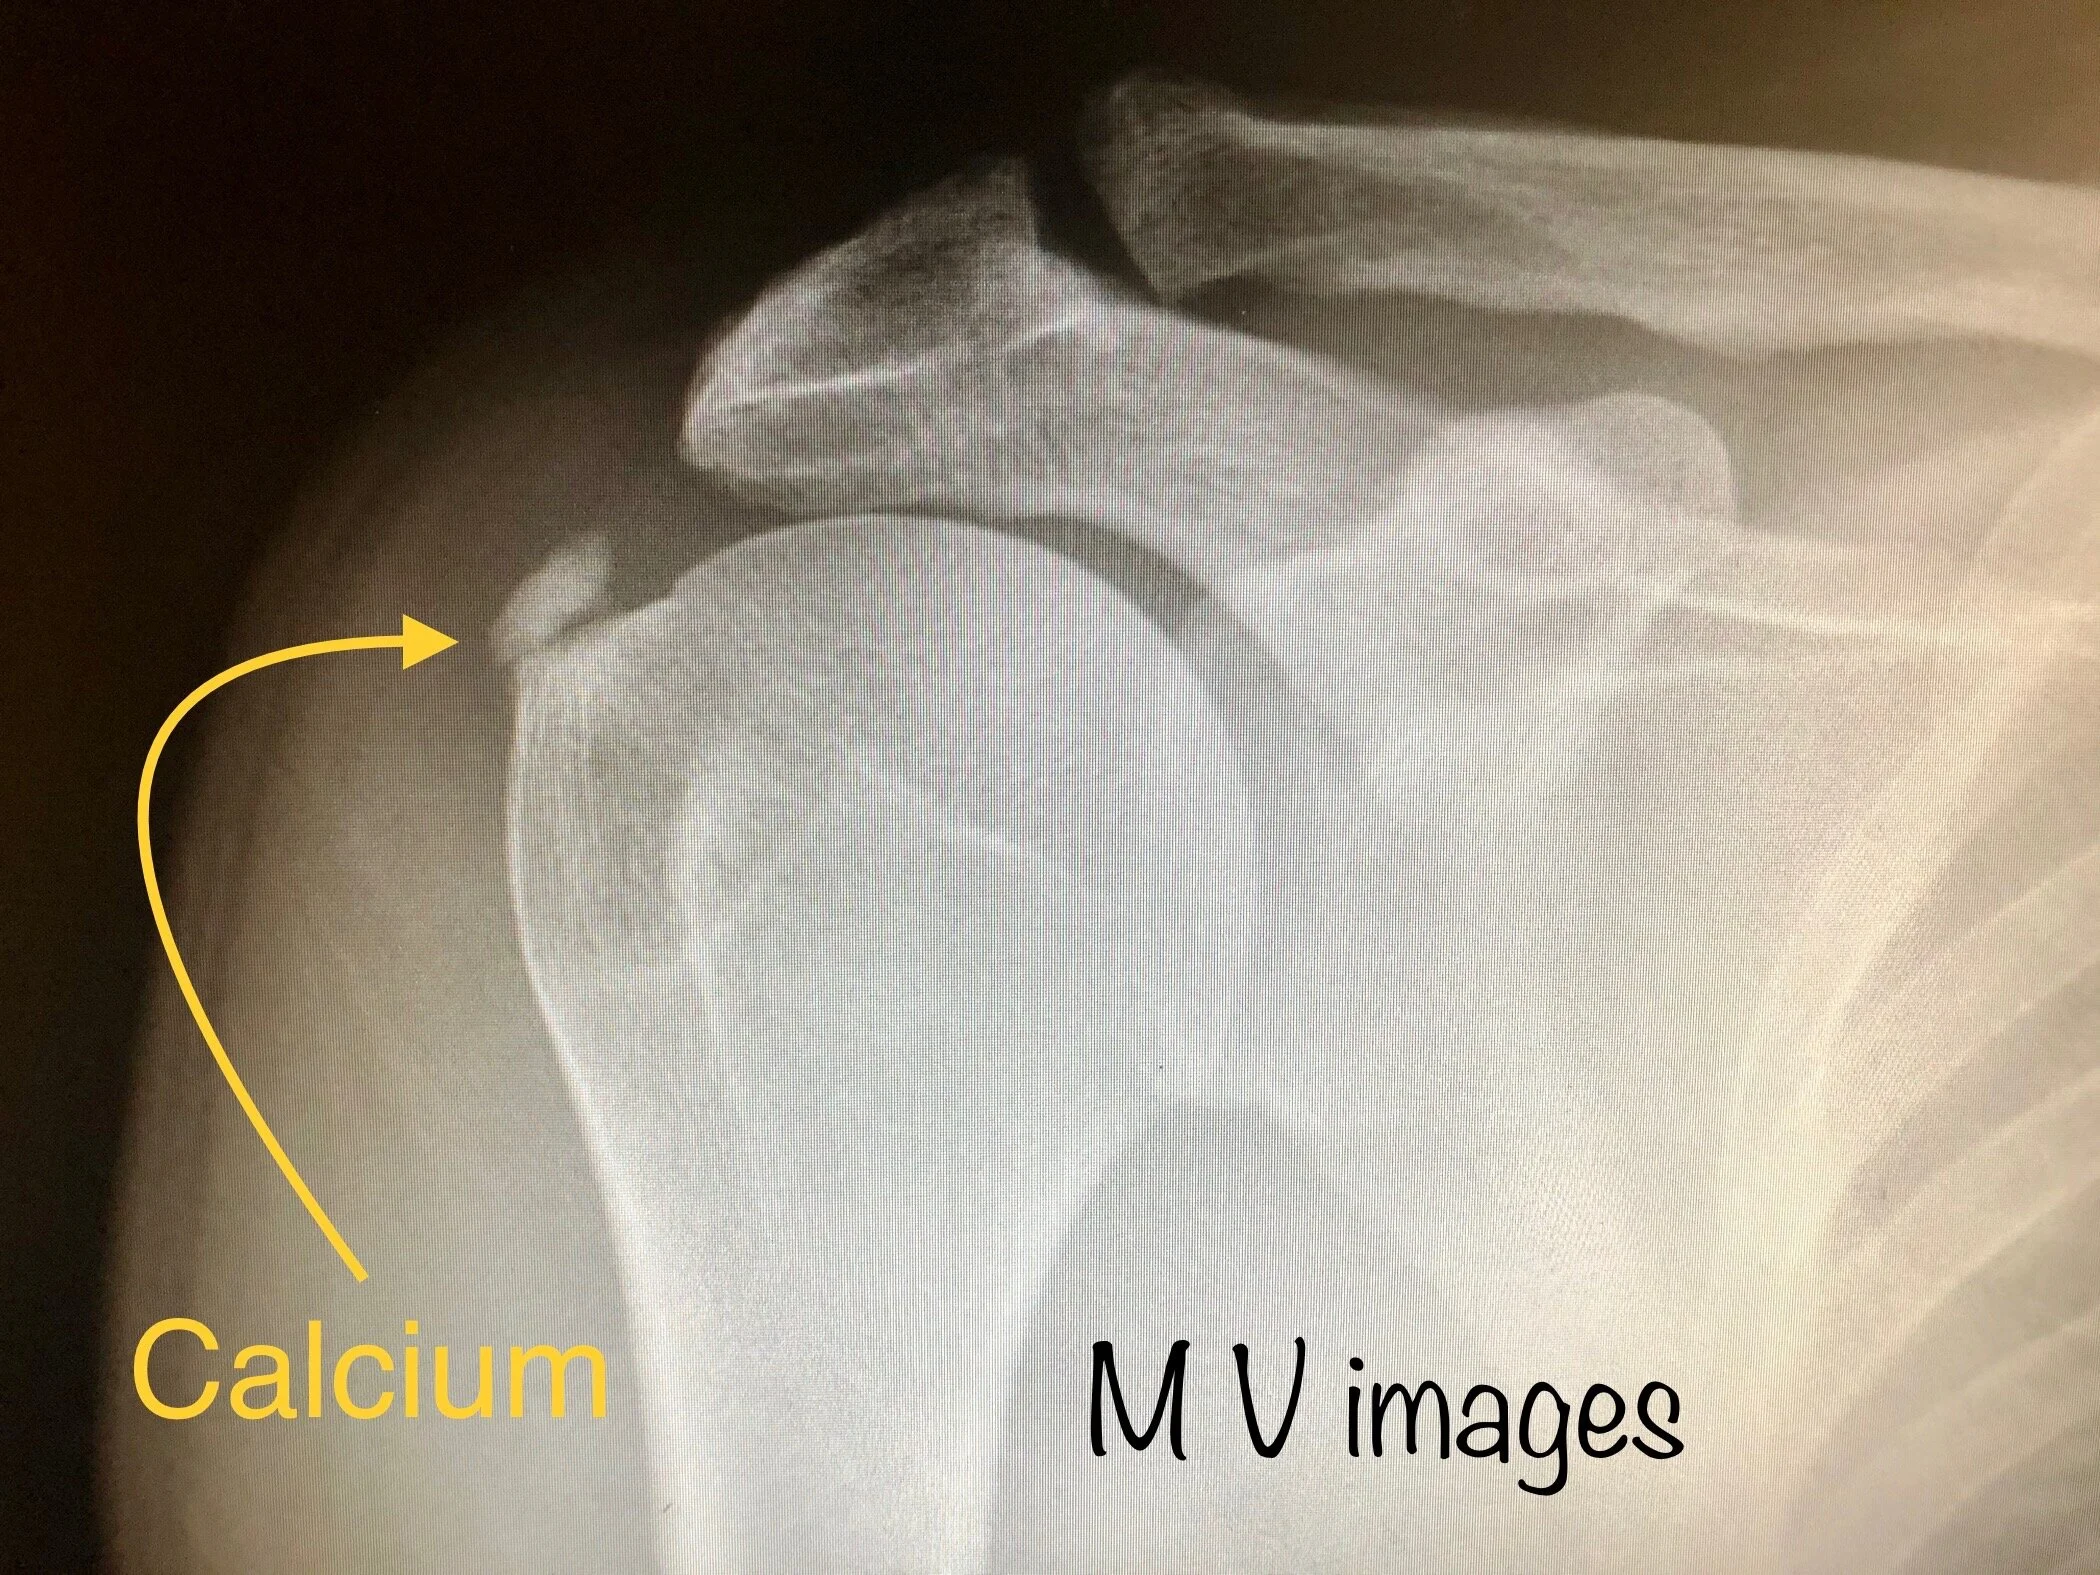

Calcific tendinitis is the build up of calcium deposits in areas of the rotator cuff tendon. Calcium deposits have a pressure effect within the tendon, can cause a chemical reaction and can also reduce space for normal movement.

Above is an X-ray of a right shoulder in a patient with a calcium deposit embedded within the tendons that move the shoulder (rotator cuff tendons)